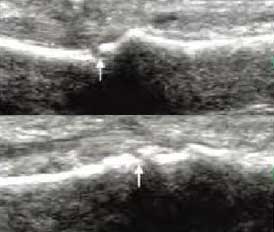

3、准确判断关节积液增加,精准判定RA严重程度

类风湿关节滑膜炎症会导致滑液渗出不断增多,形成关节腔积液。肌骨超声 少可发现1ml的积液,能对关节腔积液量及位置准确定位,通过检测判定关节腔内液性边界清楚的无回声区、细点状回声或细微的低回声条纹,判断其宽度和深度衡量积液量的多少,进而评估RA的严重程度。

Ⅰ级微量积液

滑膜囊内见前后径3.55mm液性暗区,呈椭圆形

Ⅱ级较多量积液

暗区内有团状高回声,可见深度达6.46mm液性暗区

Ⅲ级大量积液

关节囊扩张,可见大范围液性暗区,髌上囊积液深度达11.2mm